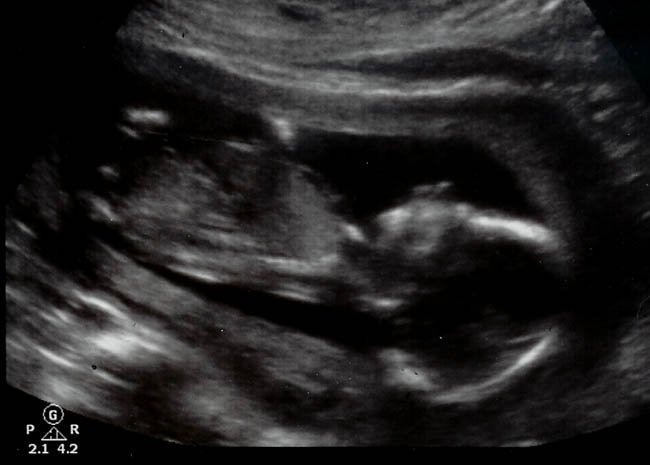

Lo cierto es que, dando un paseo por la página web de la pareja, y viendo que han publicado bastantes entradas relacionadas con el embarazo e incluso las ecografías del bebé, parece bastante evidente que la decisión será tener el hijo. De otro modo no entendería que alguien hablara de su bebé en una página web, mostrara las ecografías (incluso la 3D) y fuera tan consciente del bebé que se está formando para luego decidir abortar.

Foto | Birthornot